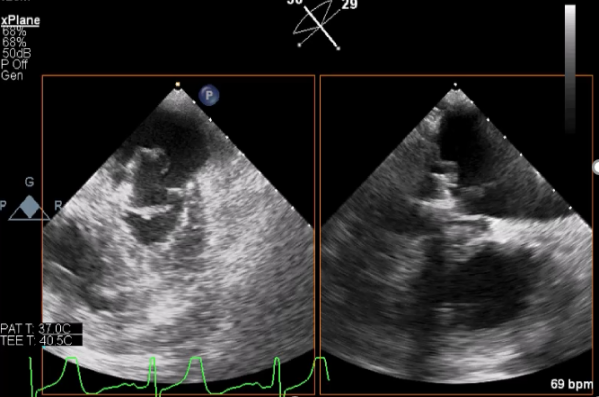

患者为71岁男性,主因“间断胸闷5年”入院,患者5年前开始出现活动后胸闷、气短,并伴有双下肢水肿,服用利尿药物治疗,症状稍好转,但仍反复发作,2016-9-5到行超声心动图提示LA 50mm,LV 65mm,RV 23mm,LVEF 65%, 二尖瓣后叶脱垂,瓣叶增厚,P2区瓣叶收缩期脱向左房,致对合不拢,三尖瓣少中量返流,收缩期前向流速最大为4.3m/s, 估测肺动脉收缩压为79mmHg,主动脉瓣二瓣化畸形,近2年规律服用诺欣妥、螺内酯、比索洛尔、托拉塞米、匹伐他汀等药物,2019-1-12到经食道超声提示:全心扩大,以左房为主,二尖瓣后叶脱垂,P2、P3区收缩期脱向左房,脱垂部分瓣叶长16mm,瓣环直径40mm,主动脉瓣增厚,黏连,开放呈左右二叶,有效瓣口面积1.4cm²,2020-12-2,行经胸超声心动图提示LA 53mm,LV 70mm,LVEF 60%,左室舒张末期容积255ml,RV 25mm,TAPSE: 正常,全心扩大,以左房为著,室壁厚度正常,运动幅度正常,二尖瓣后叶增厚,P2和部分P3区瓣膜收缩期脱向左房,脱垂瓣叶宽约17mm,脱垂间隙约12mm,瓣尖可见甩动腱索残端,瓣关闭对合不拢。

既往史:支气管哮喘

手术过程

患者麻醉方式同样采取全麻,建立静脉通路后,穿刺右侧股静脉后,预埋ProGlide缝合器后,送导管至房间隔部位,成功穿刺房间隔后进入左房,调整导管角度,顺利到达二尖瓣目标位置,后在X线及食道超声联合辅助下,宋光远教授使用2枚XTR二尖瓣夹,在精确定位后,准确夹合二尖瓣A2-P2以及A3-P3区域,患者收缩压即刻上升30mmHg,左心房收缩压由62mmHg下降至28mmHg,术中测反流面积明显减少,肺静脉多普勒波形由反向恢复正常。手术顺利结束,术后患者即刻苏醒,安返病房。

术中超声引导过程

房间隔穿刺

Bicaval 寻找穿刺点

穿刺点距离二尖瓣环4.6cm

二尖瓣联合部切面引导第一枚XTR夹子转向病变区域并逐渐进入左室

第一枚XTR夹子到达病变区域捕获瓣叶并逐渐夹闭

XTR夹子释放,残余部分返流

三维超声心动图显示第一枚XTR夹子释放,残余返流主要位于外侧

引导第二枚XTR夹子转向外侧残余病变区域并逐渐进入左室

第二枚XTR夹子释放,返流明显减少

三维超声心动图显示第二枚XTR夹子释放